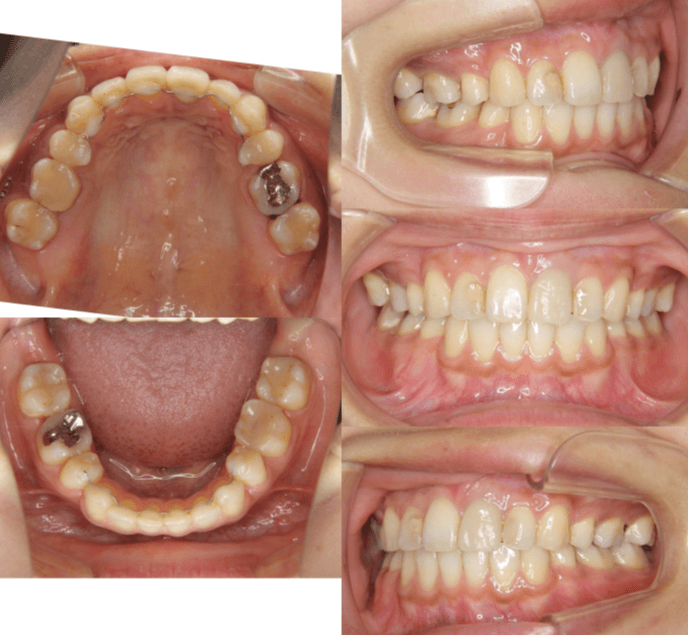

| 年齢・性別 | 34歳の女性 |

|---|---|

| 主訴 | 口元の突出感が気になり、将来的な咬合状態を整える目的で来院された患者様です。 |

| 治療期間・回数 | 3年3ヶ月・31回 |

| 費用 | 830,000円 |